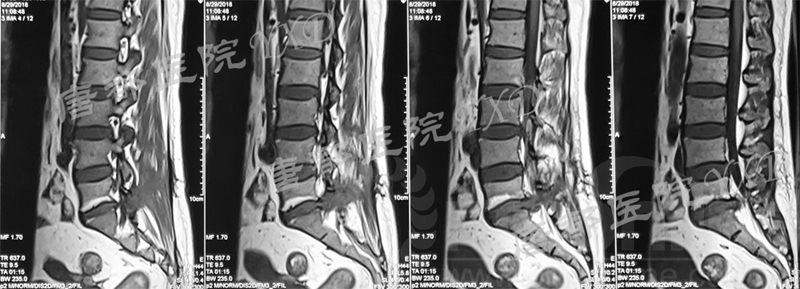

影像学检查:

诊断:腰椎椎间融合术后融合器后移

手术方案:显微镜辅助MI-TLIF腰椎翻修术

术中视频:http://api.orthonline.com.cn/attach/Case3.mp4(术中发现因前次手术全椎板及关节突切除,TLIF的第一步,即关节突关节的定位落脚点难以找到。显微镜下通过Kambin三角解剖位置,进行从外至内的解剖,寻找cage尾端;此外,因大量瘢痕渗血,难以进行充分止血;但在显微镜的照明和放大视野下,操作均可在不伤及神经的前提下进行。由于终板骨质吸收,椎间隙塌陷,导致术野内可同时看到出行根和走行根。而在显微镜下,能够通过调整景深和视线角度,精准充分处理椎间隙骨性终板。无手术并发症)